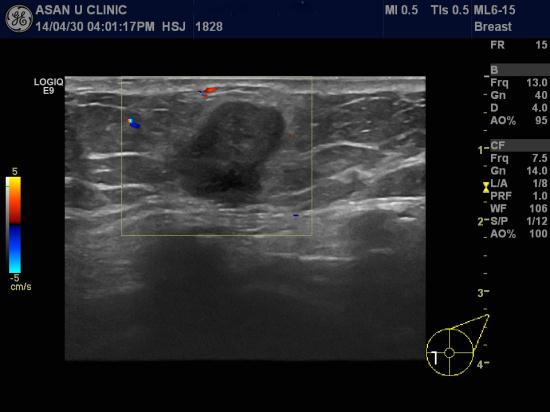

좌측유방에 갑자기 만져지는 혹으로 내원하신 89세 여성분입니다.

조직검사상 유방의 침윤성 유관암으로 진단되어 수술진행할 계획입니다.

초음파상 겨드랑이 림프절은 괜찮아 보이나 정확한 것은 수술해봐야 알수 있습니다.